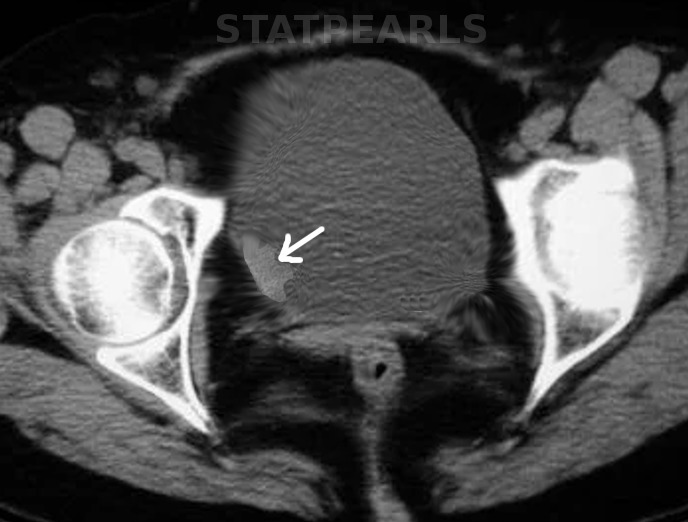

图1: 膀胱癌。图片由 S Bhimji MD 提供